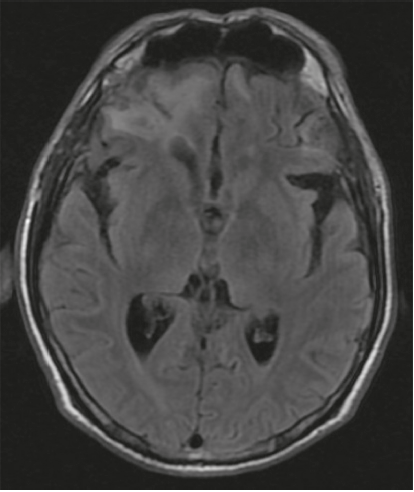

Se realizó un test de MoCA, que puntuó 14/30, a expensas de planeación, secuenciación, atención sostenida, praxis visuoconstruccional, evocación diferida y orientación temporoespacial. El deterioro cognitivo mostraba un patrón de predominio disejecutivo. La resonancia cerebral mostró una extensa zona de contusión hemorrágica en BA 10 y BA 11 en el hemisferio derecho y en giros rectos bilateralmente; se apreciaba extensión a la sustancia blanca profunda (figura 2).